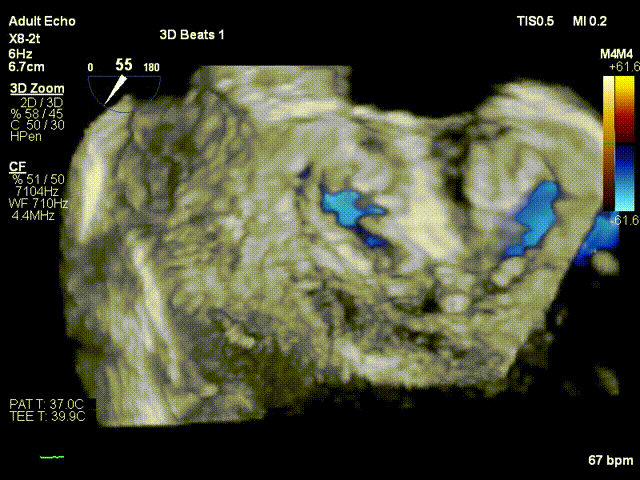

行TEE示:功能性重度二尖瓣反流、二尖瓣口舒张期几何面积 4.41cm²、收缩期二尖瓣口偏心性反流束缩流颈宽度7.2mm、PISA定量瓣口EROA=0.58cm²。STS评分高达22.1%。患者虽然为终末期心衰,二尖瓣反流量多,根据COAPT研究的结论, 患者具有TEER手术指征,考虑患者等待心脏移植一年,未有供体,但患者病情危重,心功能持续恶化,厦心结构性心脏病团队决定为患者实行经导管二尖瓣钳夹术。

基线view